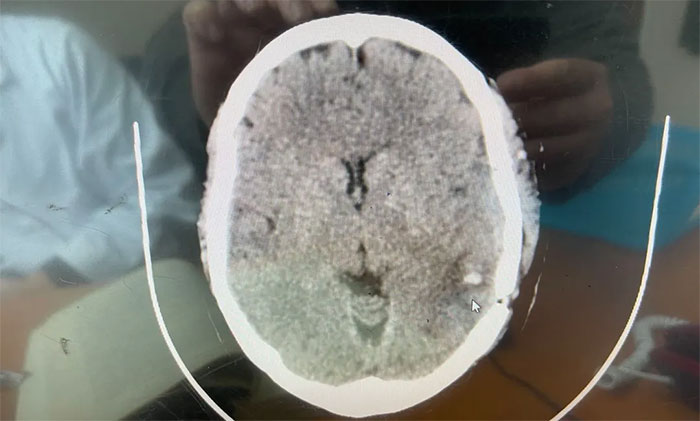

▲术后CT示海绵状血管瘤已被切除